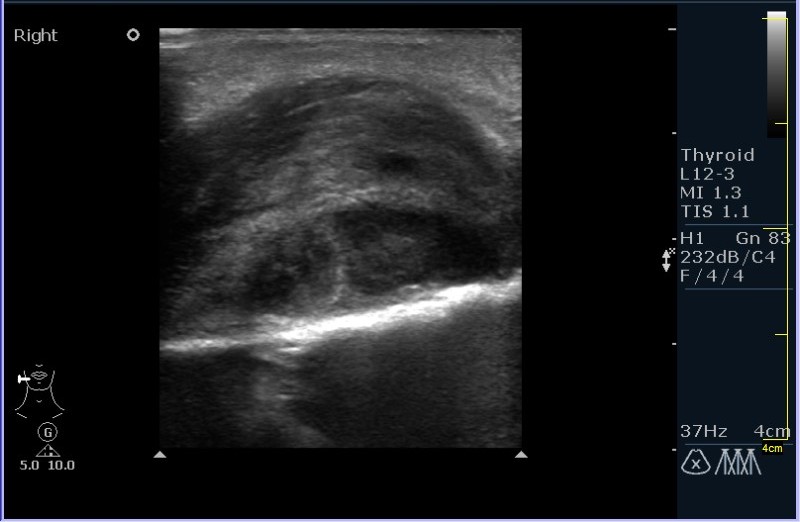

УЗИ области правой околоушной железы и угла нижней челюсти.

Девочка 8 лет, с опухлостью щеки и области правого угла нижней челюсти, резко боезненной при пальпации. В анамнезе (после наводящих вопросов :ugeek: ), визит к стоматологу около месяза назад.